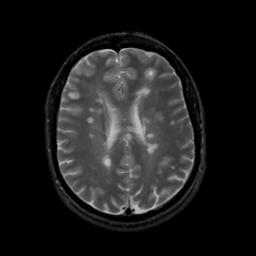

MR Study #13, May 19, 1991 -- Slice #32

[Home][Help][Clinical][Tour 1][Tour 2] Slice 32